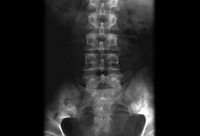

ხერხემლის სხეულის ღერძული ხედი, რომელიც აჩვენებს ცენტრალურ სპინალურ სტენოზს

BMJ 2008; 337:a2718; გამოიყენება ნებართვებით